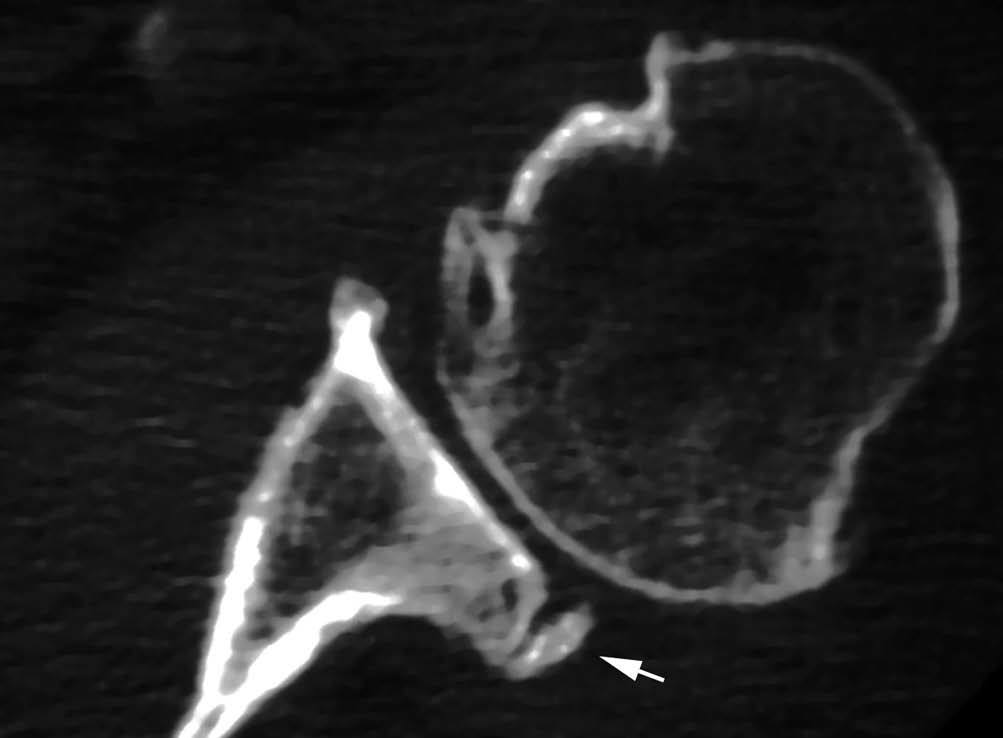

POLPSA (posterior labral periosteal sleeve avulsion)

Esta lesión se asemeja a la ALPSA, pero ocurre en el borde glenoideo posterior. El LG se halla desplazado hacia dentro y por detrás del borde glenoideo posterior. El mecanismo de producción del POLPSA es una dislocación posterior, y por tanto se puede encontrar también un Hill Sachs invertido19 (fig. 14).

. Artrorresonancia axial T1 con supresión grasa donde se observa una rotura del labio glenoideo posterior con desplazamiento posteromedial (flecha). Nótese la situación del labio glenoideo en comparación con una rotura sencilla, no desplazada, que se observa en la figura 13. Obsérvese la presencia de una lesión de Hill-Sachs invertida (cabezas de flecha), en relación con una dislocación posterior con reducción.Lesión de Bennett